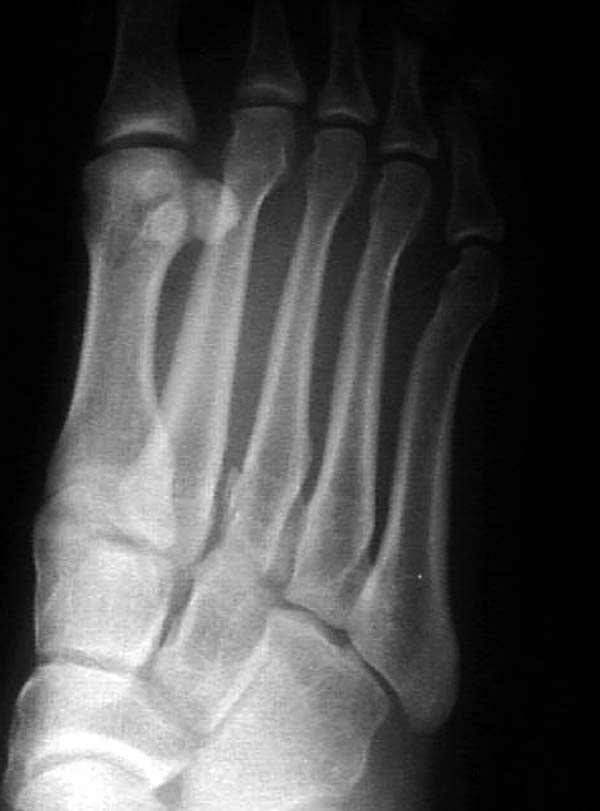

Ренген снимки прислал один из моих коллег из бывшего союза, просит совета. К нему в клинику обратился с жалобами 24 летний студент, получил травму две недели назад катаясь на скейтинг борд.

Ходить прихрамываясь на конечность. Небольшая отечность на тыле стопы, неврологических и сосудистых изменений нет. Подскажите, что предпринимать больному? Снимки представлены. Djoldas Kuldjanov, MD Department of Orthopedic Surgery St. Louis University Medical Center